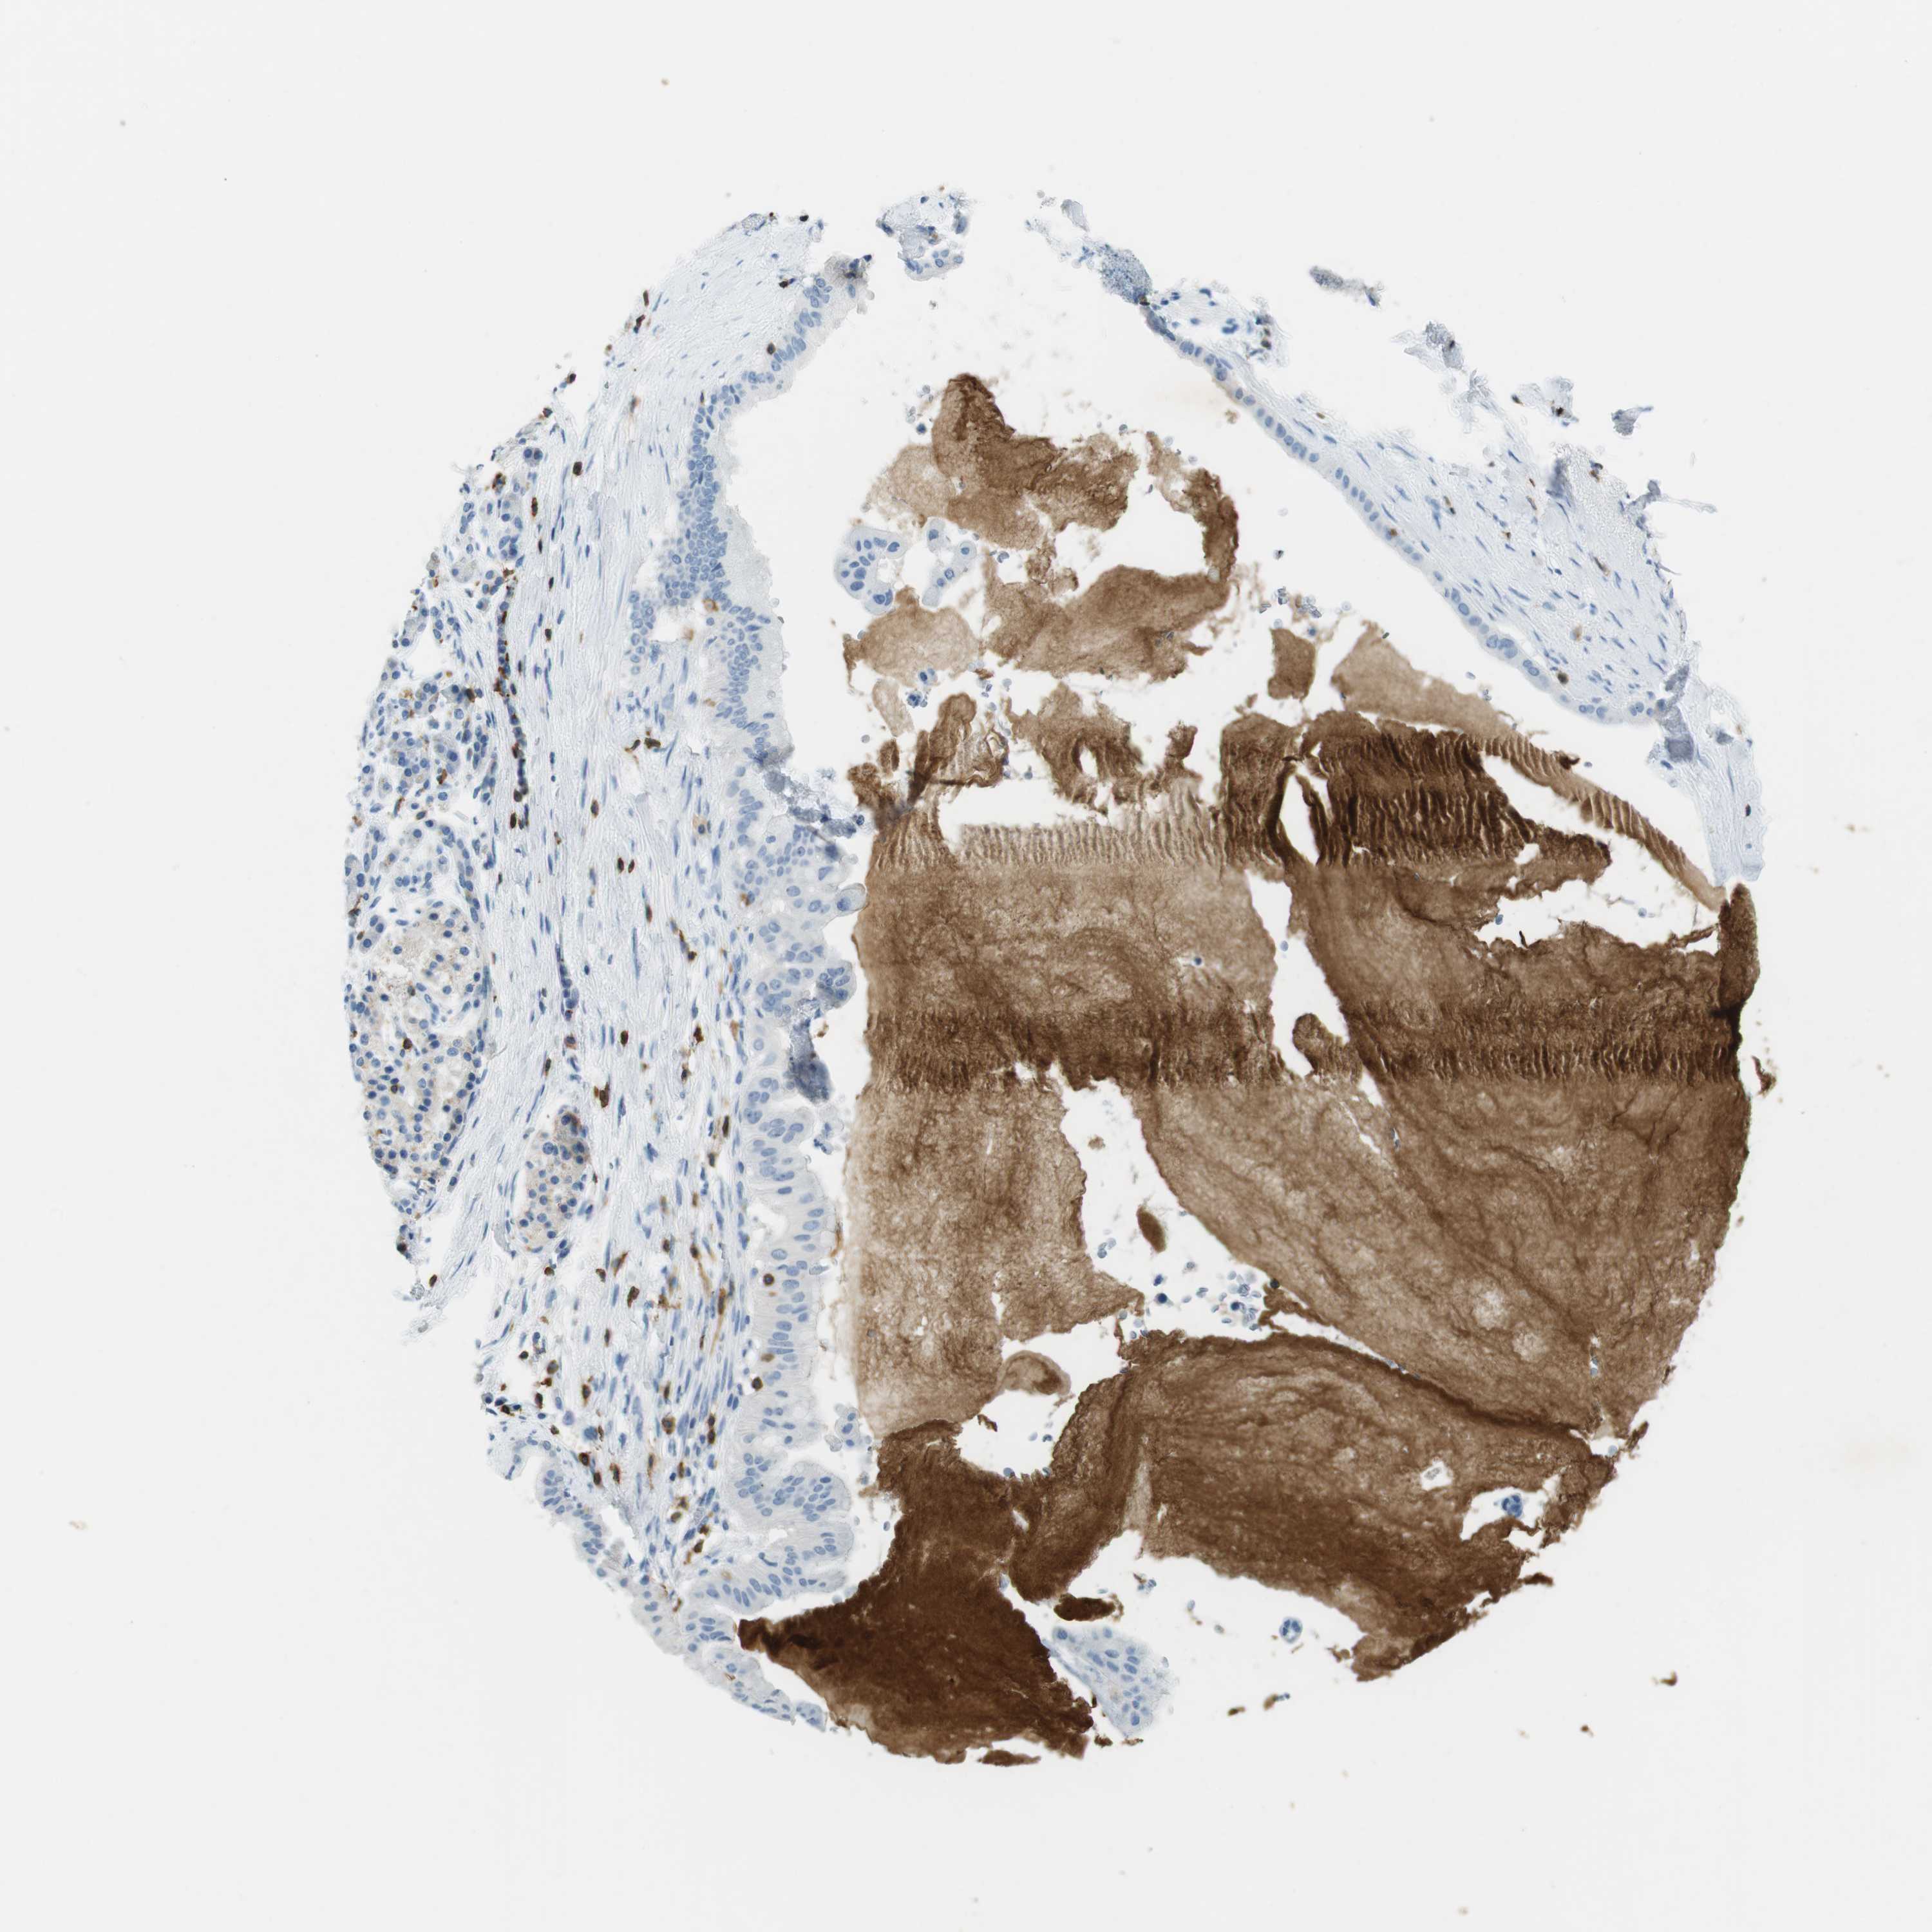

PANCREATIC CANCER - Protein expressioni

A mouse-over function shows sample information and annotation data. Click on an image to view it in a full screen mode. Samples can be filtered based on level of antibody staining by selecting one or several of the following categories: high, medium, low and not detected. The assay and annotation is described here.

Note that samples used for immunohistochemistry by the Human Protein Atlas do not correspond to samples in the TCGA dataset.

Antibody stainingi

Antibody staining in the annotated cell types in the current human tissue is reported as not detected, low, medium, or high, based on conventional immunohistochemistry profiling in selected tissues. This score is based on the combination of the staining intensity and fraction of stained cells.

Each image is clickable and will lead to virtual microscopy that enables deeper exploration of all samples and also displays staining intensity scores, fraction scores and subcellular localization as well as patient and tissue information for each sample.

Antibody HPA011157

Antibody CAB002223

Antibody CAB012978

Antibody CAB079960

Staining

High

Medium

Low

Not detected

Intensity

Strong

Moderate

Weak

Negative

Quantity

>75%

75%-25%

<25%

None

Location

Nuclear

Cytoplasmic/membranous

Cytoplasmic/membranous,nuclear

Adenocarcinoma, NOS

Adenocarcinoma, metastatic, NOS